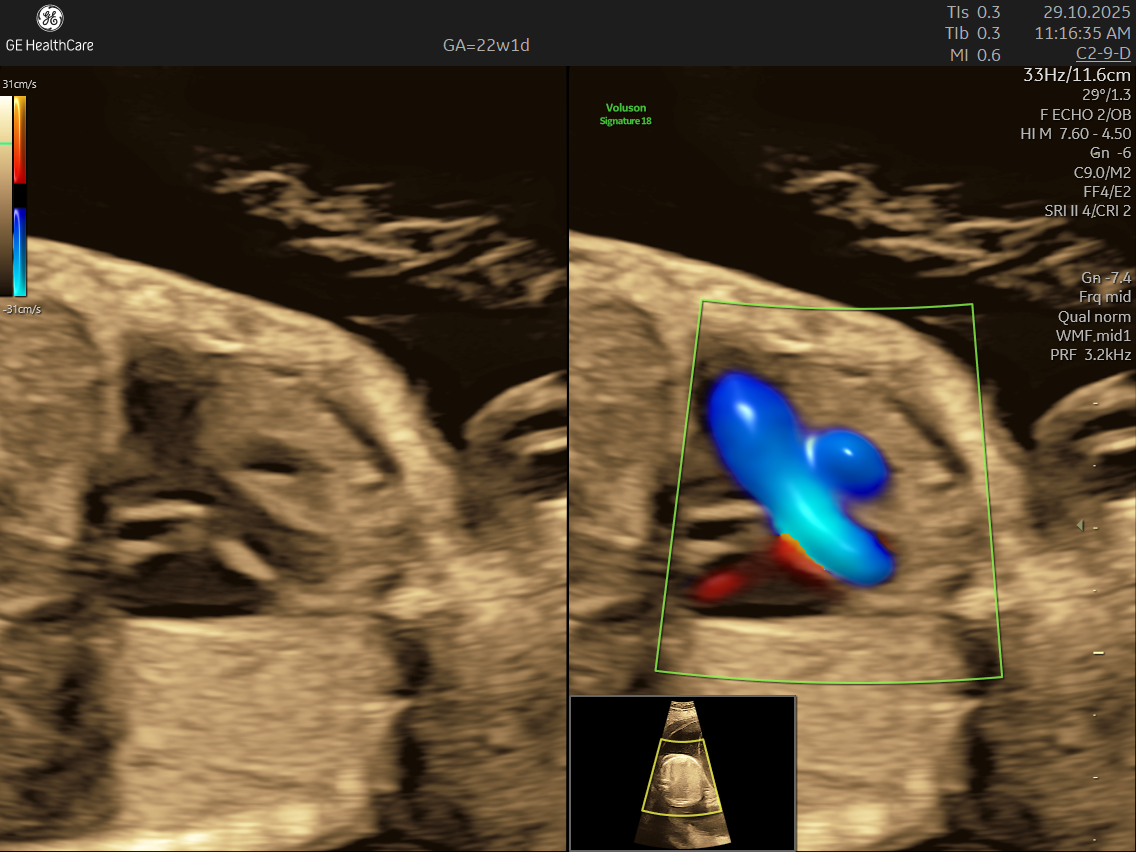

- High Detail: Utilizing advanced Doppler ultrasound technology, it tracks blood movement through the heart and valves, highlighting issues that general scans often cannot detect.

- Blood Flow Patterns: Detects arrhythmias or irregular heartbeats and checks for efficient circulation through the heart and major vessels.

- Abnormalities in blood flow patterns and valve function observed on Doppler imaging.

- Using the advanced GE Voluson S10 ultrasound machine—renowned for its superior imaging clarity, 4D real-time visualization, and automated analysis tools that significantly increase diagnostic accuracy and reduce the chances of missing subtle heart defects.

- Its a specialized ultrasound done between 18–24 weeks of Gestational Age that evaluates the structure, function, and rhythm of a baby’s heart while still in the womb. This scan uses high-frequency sound waves to create detailed images of the fetal heart, aiding in the detection of congenital heart defects (CHDs) and other abnormalities.